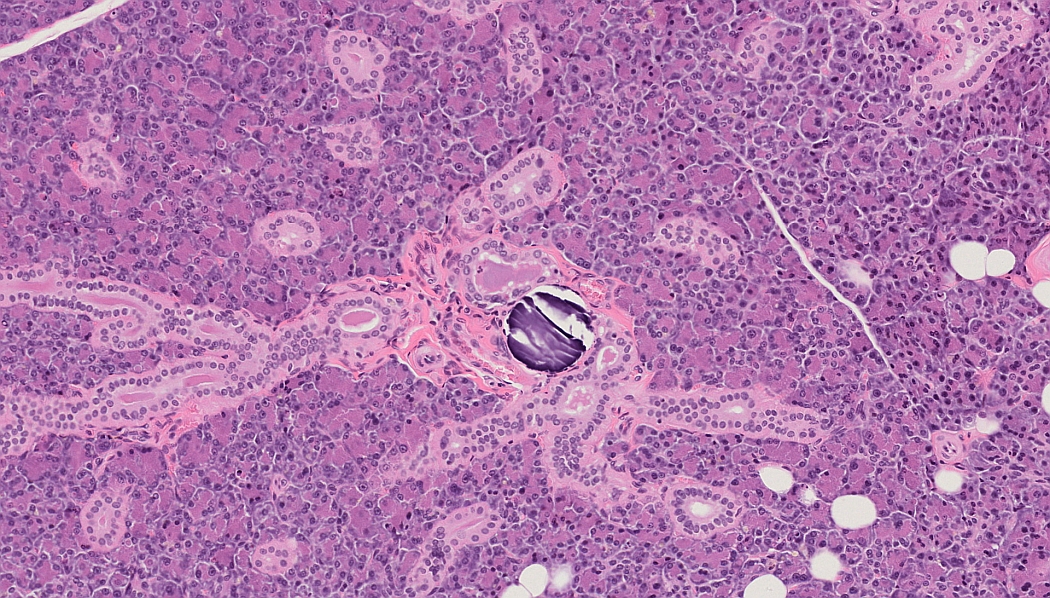

Guess What! - Glands of the Head and Neck Region, Background Findings

Which organ is it?

Salivary gland: Parotid gland

Which species is it?

Rat

What is the diagnosis?

Calculus, duct